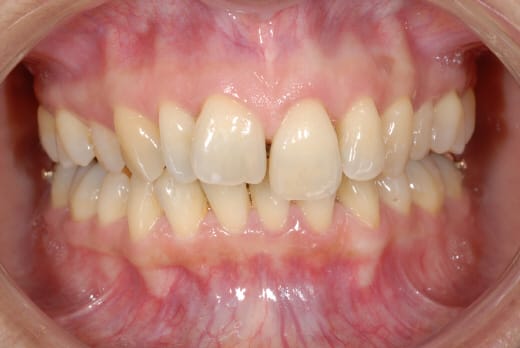

ben voilà des news en photo...

(et que personne me sape le moral...)

ensuite si vous promettez de pas vous foutre de ma gueule j'envoie une photo vue de face, pour que vous voyiez ce que c'est que un sourire qui tue la mort :-)))